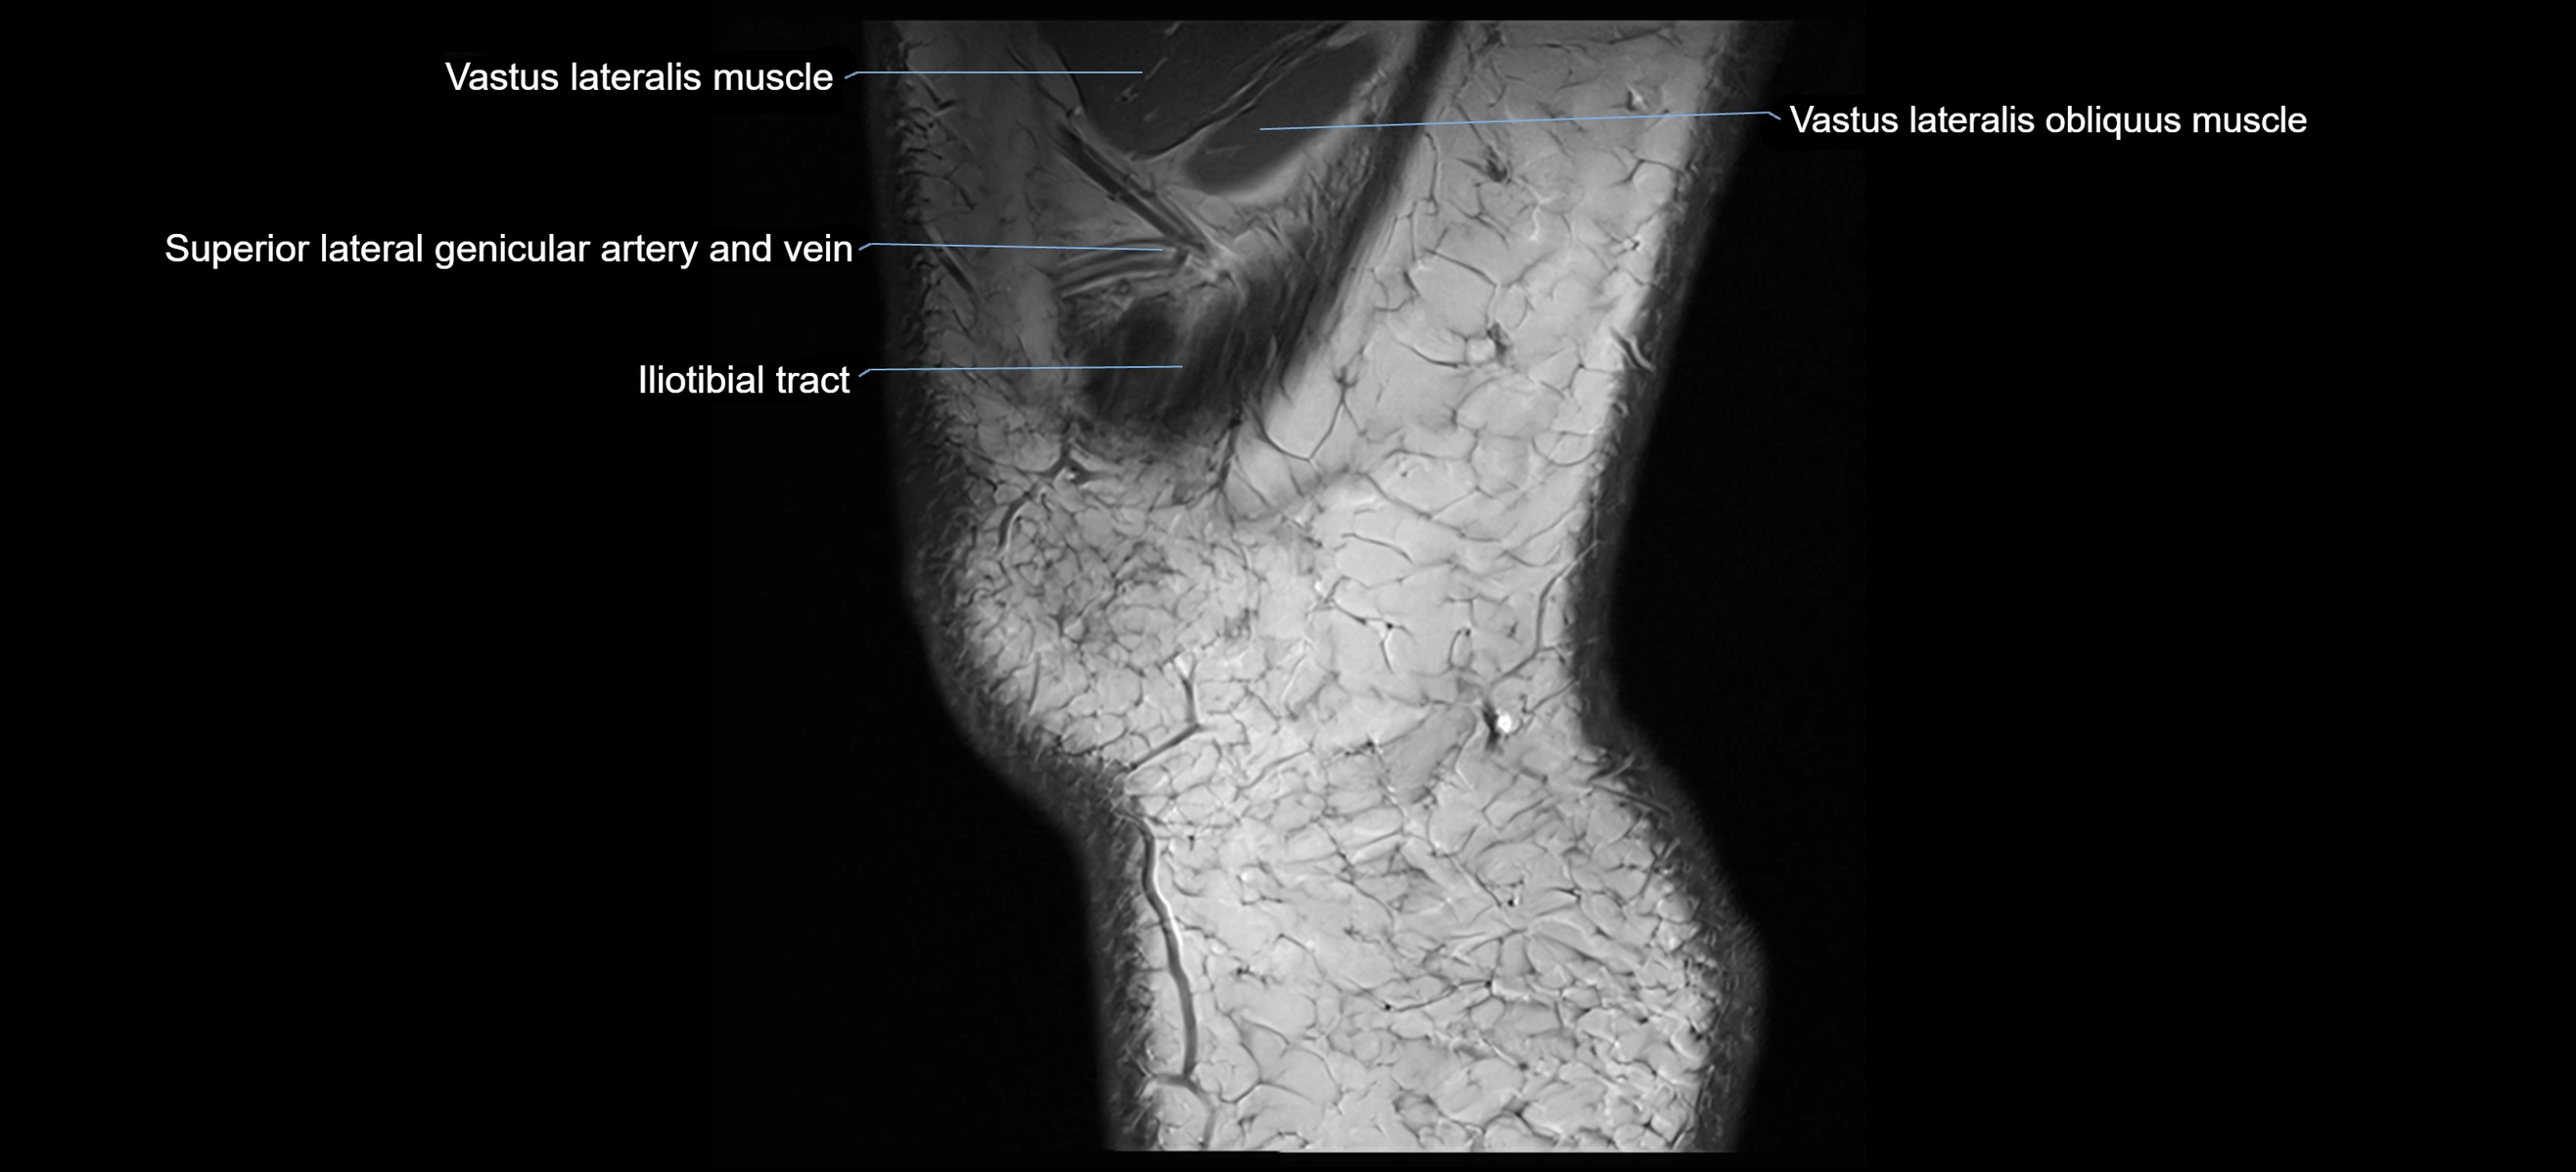

- Vastus Lateralis Obliquus Muscle

- Vastus lateralis muscle